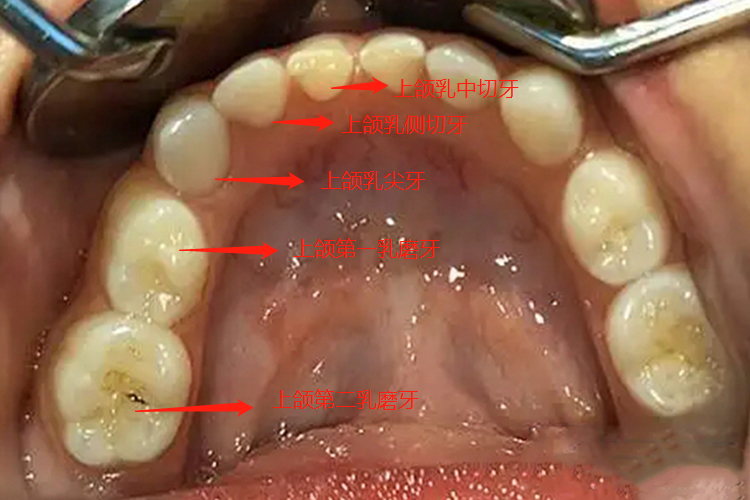

上乳牙即上颌乳牙,共有10个,左右两侧各5个,从中线起到两旁,分别为乳中切牙、乳侧切牙、乳尖牙、第一乳磨牙、第二乳磨牙。

人一生中有两副天然牙,萌出时间早的为乳牙,上乳牙即上颌乳牙,共有10个,左右两侧各5个,从中线起到两旁,分别为上颌乳中切牙、上颌乳侧切牙、上颌乳尖牙、上颌第一乳磨牙、上颌第二乳磨牙。